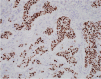

Apocrine change is recognised in benign, atypical and malignant lesions of the breast. Apocrine metaplasia, a frequent finding in the breast of women over the age of 25 years, is most commonly seen in benign cysts with a simple or papillary configuration. Apocrine change is also recognised in other benign lesions including sclerosing adenosis, now known as apocrine adenosis. Apocrine atypia usually refers to cytological atypia in which there is at least threefold variation in nuclear size but architectural atypia may also occur. The distinction between atypical apocrine hyperplasia and non-high-grade apocrine ductal carcinoma in situ may be difficult due to the relative rarity of these entities and the lack of validated diagnostic criteria. Lobular carcinoma in situ (LCIS) with apocrine change is considered to be a variant of pleomorphic LCIS. An apocrine variant of encapsulated papillary carcinoma is also recognised. Apocrine change is described in invasive carcinoma, including no special type, lobular, micropapillary and mucinous variants. The recent WHO 2019 update recognises 'carcinoma with apocrine differentiation' as a special type breast carcinoma based on the presence of apocrine morphology in at least 90% of the tumour. Tumours with apocrine morphology are usually but not always hormone receptor negative. Human epidermal growth factor receptor 2 (HER-2) status is variable. Molecular studies have identified breast tumours with apocrine features and high expression of androgen receptor mRNA including 'luminal androgen receptor tumours' and 'molecular apocrine tumours'. The term 'pure apocrine carcinoma' has been proposed to describe an invasive carcinoma with apocrine morphology that is oestrogen and progesterone receptor negative and androgen receptor positive. HER-2 status may be positive or negative. This article reviews the pathology of benign, atypical and malignant apocrine lesions of the breast, with emphasis on diagnostic criteria including an approach to evaluation of apocrine lesions on needle core biopsy, and recent advances in our understanding of invasive apocrine carcinoma.